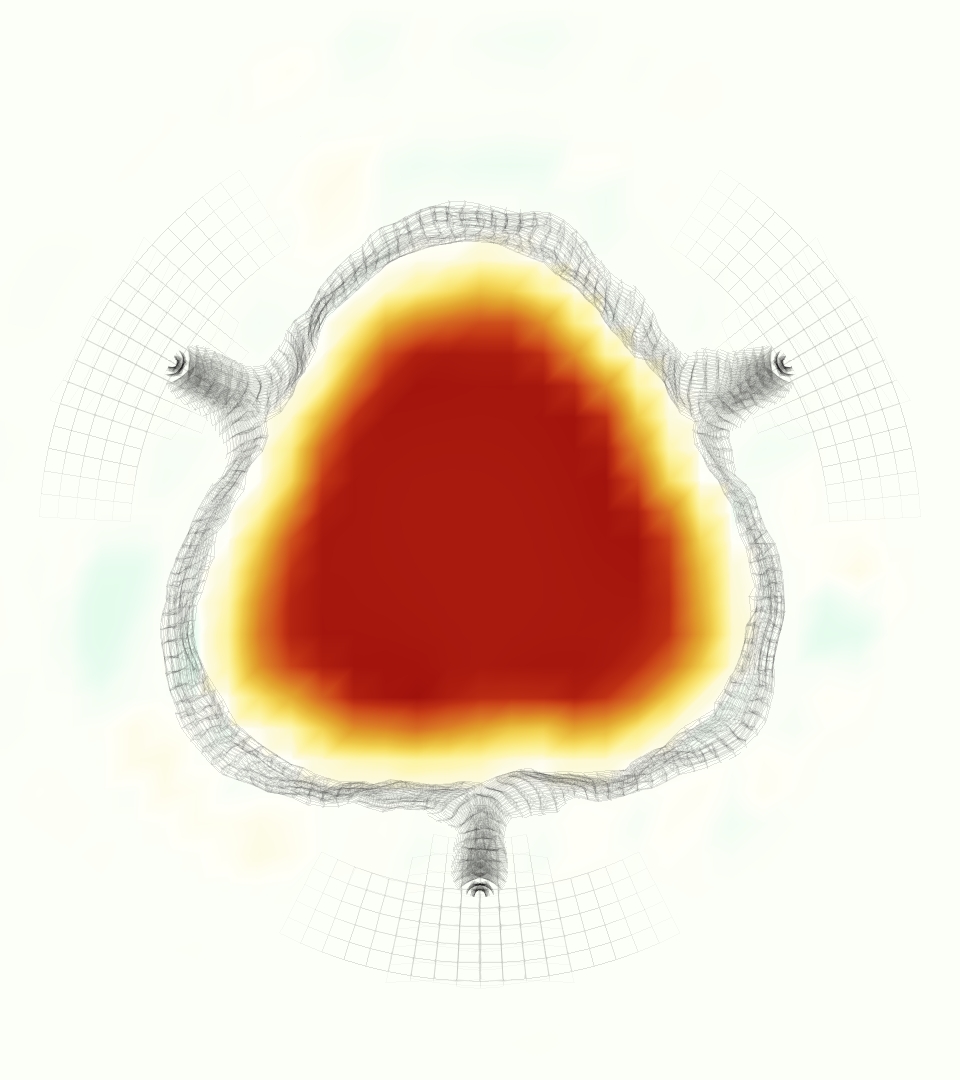

The gross morphology of the model valve that emerged from this process is shown in Figure 4. The free edge was 2.87 cm, corresponding to 3.3 cm in the predicted loaded configuration. After the pinching the leaflets together at the commissures, this left approximately 2.1 cm of free edge rest length per leaflet free to move independently of the other leaflets, within measurement error of ±0.1 cm from the free edge length of 2.2 cm measured on the prostheses. The leaflet rest height was 0.94 cm corresponding to a predicted loaded height of 1.44 cm. The measured leaflet height of 1.3 cm is nearly the predicted loaded height of 1.44 cm, which may be because the leaflets are so compliant in the radial direction, that pulling them flat to measure them achieved substantial stretches. The fiber orientation of the model runs from commissure to commissure and qualitatively matches experimental observations [38], though direct quantitative comparison is beyond the scope of this work. One minor limitation is that we do not add bending rigidity to the leaflets, beyond what emerges from the thickening process described above, and thus may not accurately capture leaflet flutter or other similar behaviors. Based on the thickness of mm, we estimated the mean tangent modulus at the predicted loaded stretches as dynes/cm2 circumferentially and dynes/cm2 radially. The prosthetic valve tissue is fixed in glutaraldehyde, and literature values for the fully-recruited circumferential tangent modulus of fixed porcine aortic valve tissue vary widely. Based on the experimental measurements of Billiar and Sacks and their constitutive law for valves fixed under 4 mmHg of pressure, we evaluated their constitutive law at the relevant stretches and and estimated the circumferential tangent modulus to be dynes/cm2 [6]. Rousseau et al. reported moduli ranging from to dynes/cm2, depending on the applied preload during fixation [36]. Sung et al. reported moduli ranging from to dynes/cm2, depending on fixation pressure [43]. Thus our estimated tangent modulus falls within the range of existing studies, so we considered our resultant modulus in good agreement given the complexity of the steps involved, phenomenological nature of the constitutive law and uncertainties in experiments. We do not have access to the precise material properties of the prosthetic valve, and further, the only literature we could find on the material properties of a similar prostheses reported the tangent modulus at one particular loading, which did not appear to be at a relevant stretch for comparisons with our model [19]. Thus, our model has material properties in a reasonable range for a fixed aortic valve prostheses (placed in the pulmonary position in our simulations), but it does not directly model the material properties of the prostheses.

We constructed the model vessel for FSI simulations from data from the MRI scans (Figure 4). The signal magnitude of 3D printed model material is distinct from the signal of the fluid in the scans, and we applied a thresholding operation to generate a three-dimensional model of the printed vessel surface. Using the MRI data ensured that the MRI and simulation coordinates were consistent in space and there were no alignment or registration errors. While using the files that generated the 3D printed model would have offered more spatial fidelity, the potential error in flow fields due to any mis-registration would have likely been much more substantial. Using Meshmixer (San Rafael, CA), we smoothed the mesh to remove stair-step effects and removed artifacts from the valve scaffold. We then remeshed to the desired edge length of 0.25 mm and extruded the model 0.25 mm and 0.5 mm to create a three-layer structure. As in the valve, this serves to eliminate the “grid aligned artifact” that can occur with pressure differences across thin membranes in the IB method [16]. Flow extenders of length 1 cm were added to the vessel at the inlet and both outlets to ensure that the normal to the vessel was aligned with the normal of the fluid box at the inlets and outlets. In FSI simulations, the vessel was held in place using target points, stiff springs of zero rest length that connect the current position of each model node to its desired position (Section 3.3). Additional linear springs are placed on each edge in the triangulated model. These springs are not meant to model a particular material and only serve to keep the vessel rigid and stationary throughout the simulation.